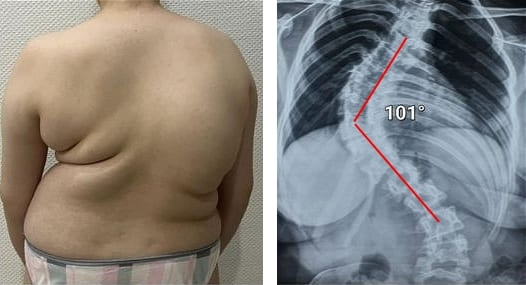

Всички стави изискват внимание, но гръбначният стълб е основният проблем. Започнете да се грижите за него преди да се появят необратими промени. В противен случай ви очакват последствия като: ХИЛО, ИЗМЕСТВАНЕ НА ГРЪБНАЧНИТЕ ИНДИВИДУАЛИ, ДЕФОРМАЦИЯ НА ГРЪБНАЧНИЯ СТЪЛБ И ПЪЛНА ЗАГУБА НА ПОДВИЖНОСТ. Не чакайте момента, когато и най-малкото движение стане болезнено и мъчително!

Погледнете тези снимки – това е съдбата на тези, които не са реагирали навреме. Днес те са безпомощни и много от тях нямат никого, който да им помогне. Наистина ли искате такъв край?

– Всеки един от тези хора е мислил, че „ще мине от само себе си“! Но ето докъде са стигнали: пълна загуба на подвижност, парализа, ампутация – доживотна зависимост от другите и ИНВАЛИДНА КОЛИЧКА! Повече от 90% от хората стават инвалиди само защото не са предприели правилните стъпки навреме. ИЗНОСВАНЕТО НА СТАВИТЕ С ВЪЗРАСТА ЧЕСТО ЗАПОЧВА БЕЗ НИКАКВА БОЛКА – като игнорирате първите симптоми, вие сами разрушавате живота си!

- Всички тези снимки показват, че гелът „Reumax” възстановява здравето на ставите, дори в случаи, когато диагнозата изглеждаше като смълртна присъда. Без хирургични интервенции, без мъчителни болки, всички пациенти успяха да постигнат стабилно подобрение и да се върнат към нормалния си живот. ТОЗИ ГЕЛ НАПЪЛНО ПРОМЕНИ ХОДА НА ЛЕЧЕНИЕТО НА СТАВИТЕ И ГРЪБНАКА!